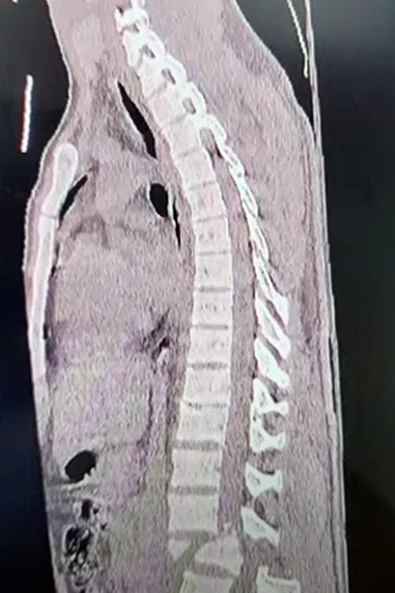

Segundo informações, o jovem estava trabalhando em uma torre de internet

rural, caiu de uma altura de 12 metros.

jovem foi socorrido e levado para o hospital em Brasiléia, o trabalhador sofreu

fratura na coluna.